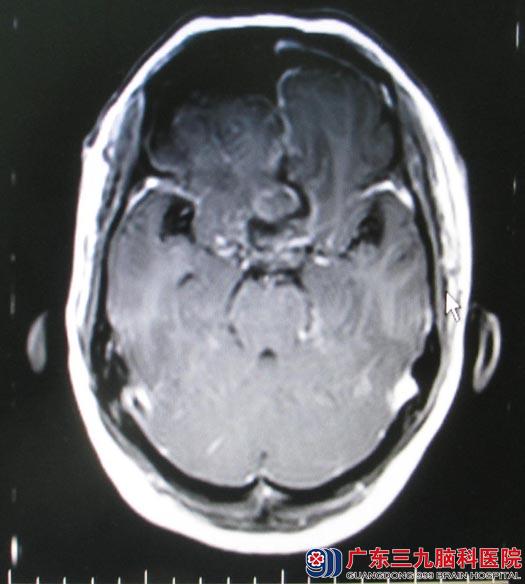

综合神经外科的鲁明主任主刀,术中取额部冠状切口,经右侧额底入路,轻掰额叶脑组织,见前颅底肿瘤呈灰白色,边界较清,质中,血供较丰富,和周围脑组织边界稍清,双侧大脑前动脉被肿瘤包绕,仔细分离后保留双侧大脑前动脉,可见肿瘤基底位于鞍结节和嗅沟后侧,沿肿瘤基底部切除肿瘤,反复电凝烧灼基底部硬膜,肿瘤经小心分离后完整切除,过程中视神经、垂体柄及下丘脑等重要结构保护完整。术后林阿姨恢复良好,视力也较术前好转,可以下床活动。术后病理结果示:过渡型脑膜瘤(WHO1级)。